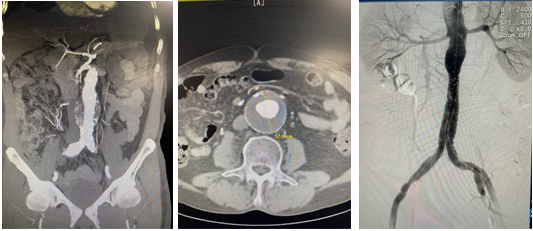

本例腹主动脉瘤患者瘤颈长度3.6cm,瘤颈角度30.7°,瘤体直径5.28cm,瘤腔内血栓直径2.9cm,右侧髂总动脉瘤直径2.02cm。患者腹主动脉瘤瘤体直径较大,瘤腔内血栓较多,瘤体破裂及血栓脱落导致远端栓塞风险高,且合并右侧髂总动脉瘤,手术指征明确。术前在代毅主任指导下,医护团队积极完善相关术前检查,并组织了多次科内术前讨论,对手术方式、术中术后的风险及并发症、术后护理等均制定了详细计划及预案,确保手术安全顺利进行。本例手术难点在于合并右侧髂总动脉瘤,且累及右髂内动脉,术中、术后易发生远端型内漏、移植物移位、肾动脉闭塞等并发症。术中需栓塞右髂内动脉,所以必须精确定位左侧髂支支架的位置,保留左髂内动脉,确保盆腔血供。经充分评估患者病情及征得患者及家属同意后,详细制定手术方案,最终顺利完成手术。